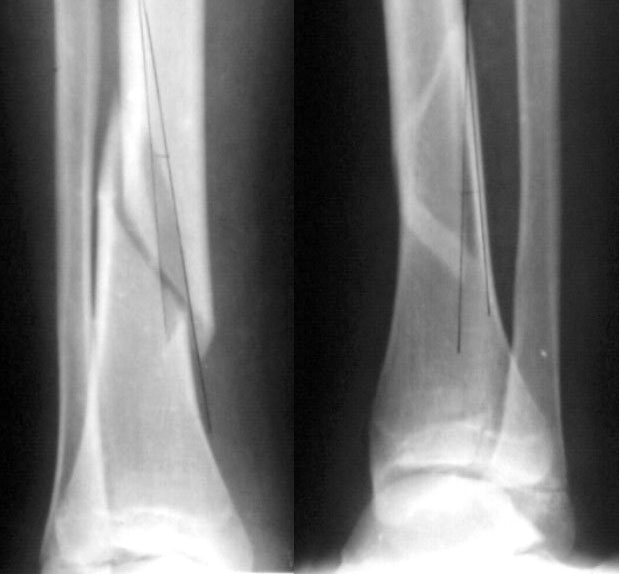

Девочка 14 лет полтора года назад оперирована в детской больнице по поводу спирального перелома костей голени (снимок 1)- выполнен закрытый остеосинтез стержнем Богданова, введенным ретроградно с медиальной стороны (снимок 2). Фиксатор после сращения удален

(см. снимки 3 и 4, после удаления, для сравнения со здоровой стороной, фас - стоя с нагрузкой на обе ноги). В настоящее время беспокоят боль и отеки в области голеностопного сустава при нагрузках, после ходьбы. В покое и ночью боли нет.Амплитуда движений в голеностопном суставе практически полная. Имеется заметная боковая нестабильность, т.е. несостоятельность дельтовидной связки и межберцоого синдесмоза. Складывается впечатление, что при остеосинтезе был отколот и смещен в сторону сустава костный фрагмент позади внутренней лодыжки, увеличилось смещение отломка заднего края, что привело к столь ранним проявлениям деформирующего артроза. Встает вопрос - что делать сейчас?Артодез - наверно, рано. Ревизию сустава, моделирующую резекцию?Пластику связок? Что-то еще? Заранее спасибо.